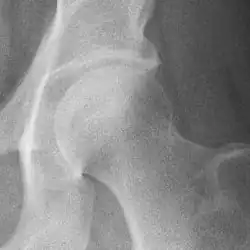

Osteoarthritis of the hip joint may also be graded by Tönnis classification. There is no consensus whether it is more or less reliable than the Kellgren-Lawrence system.[8]

Severe (Tönnis grade 3) osteoarthritis of the hip.

severe joint space narrowing, or joint space obliteration

severe deformity of the head